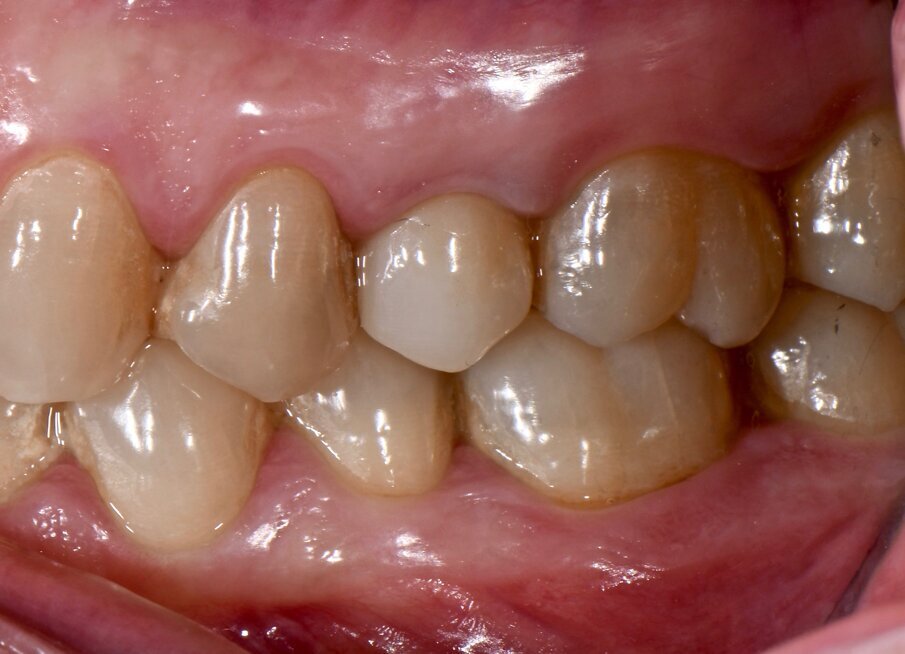

Il riscontro a 1 anno ha dimostrato una stabilità clinica per ciò che concerne il FMPS e il FMBS se comparata ai dati presi a 6 mesi. Il valore medio della profondità di sondaggio, invece, è ulteriormente migliorato di 0.34 mm e 0.67 mm rispettivamente per gli impianti 15 e 25. La rivalutazione dei parametri parodontali a 6 mesi e 1 anno è stata riportata nelle Figure 5a-6 e in Tabella 1.

Fig. 5a - Condizione clinica ad 1 anno: visione frontale.

Fig. 5b - Condizione clinica ad 1 anno: I e VI sestante.

Fig. 5c - Condizione clinica ad 1 anno: III e IV sestante.

Fig. 6 - Charting parodontale a 1 anno.